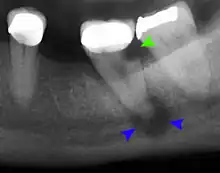

Mouth infections are usually diagnosed on history and physical exam in the dental office or at a clinic visit with an otolaryngologist.[1] Swelling within the oral cavity or cheeks, along with a history of progressively worsening tooth pain and fevers, is usually enough evidence to support the diagnosis of a mouth infection. Depending on the severity of the infection, further tests may include x-rays and CT scans of the mouth to better characterize the location and extent of the infection.[12] If the infection is drained with a needle or scalpel, then a swab of the infection is collected to identify the microbes present in the abscess and to determine their respective susceptibilities to antibiotics. Other lab tests may include a complete blood count with differential, serum electrolyte concentrations, and other routine assays for an infectious workup.[1][2]